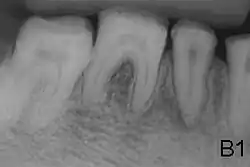

X-ray showing lack of enamel opacity and a pathological loss of enamel in patient with amelogenesis imperfecta

Enamel defect due to malfunction of enamel calcification, therefore enamel is of normal thickness but is extremely brittle, with an opaque/chalky presentation. Teeth are prone to staining and rapid wear, exposing dentine. Condition is of autosomal dominant and autosomal recessive pattern. Enamel appears less radioopaque compared to dentine on radiographs.